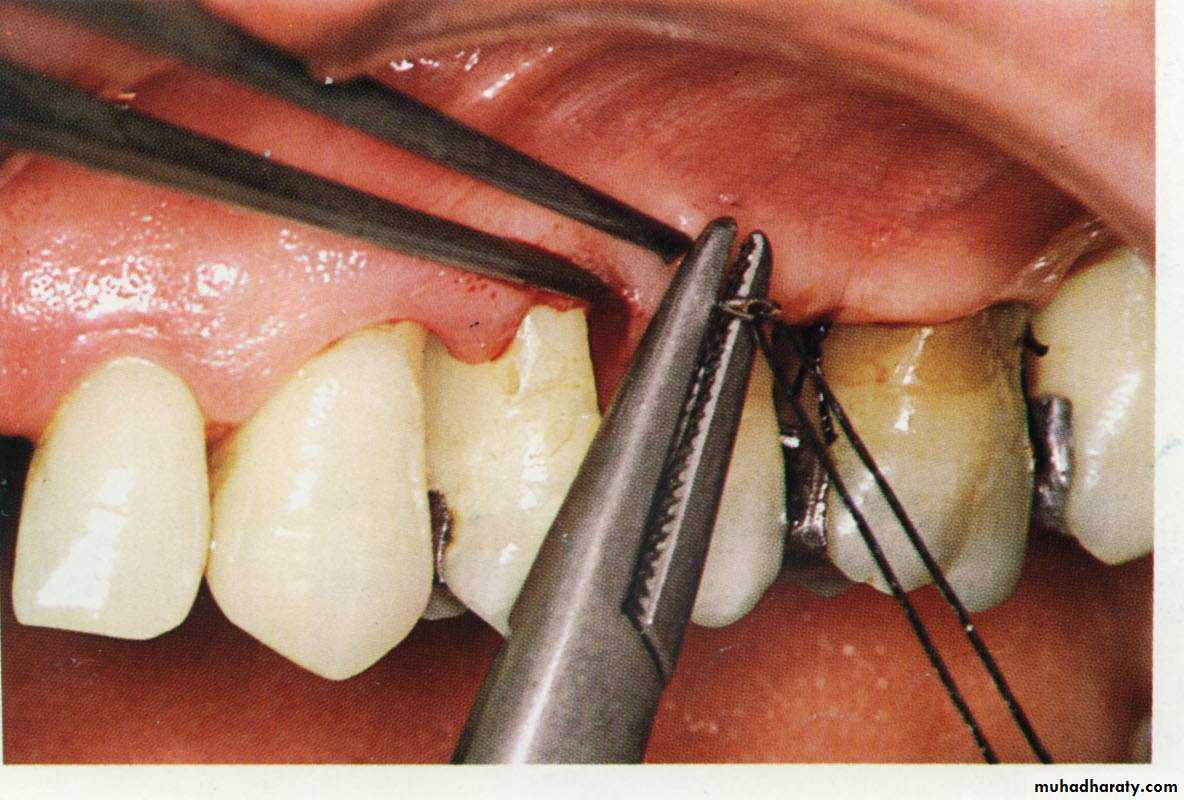

The flap is then reflected, and all the tissue around and between the teeth should be removed. Thorough root planning and cleaning of the infra-bony pocket can be performed.

The flap margins are now sutured again and the area can then covered with periodontal pack.